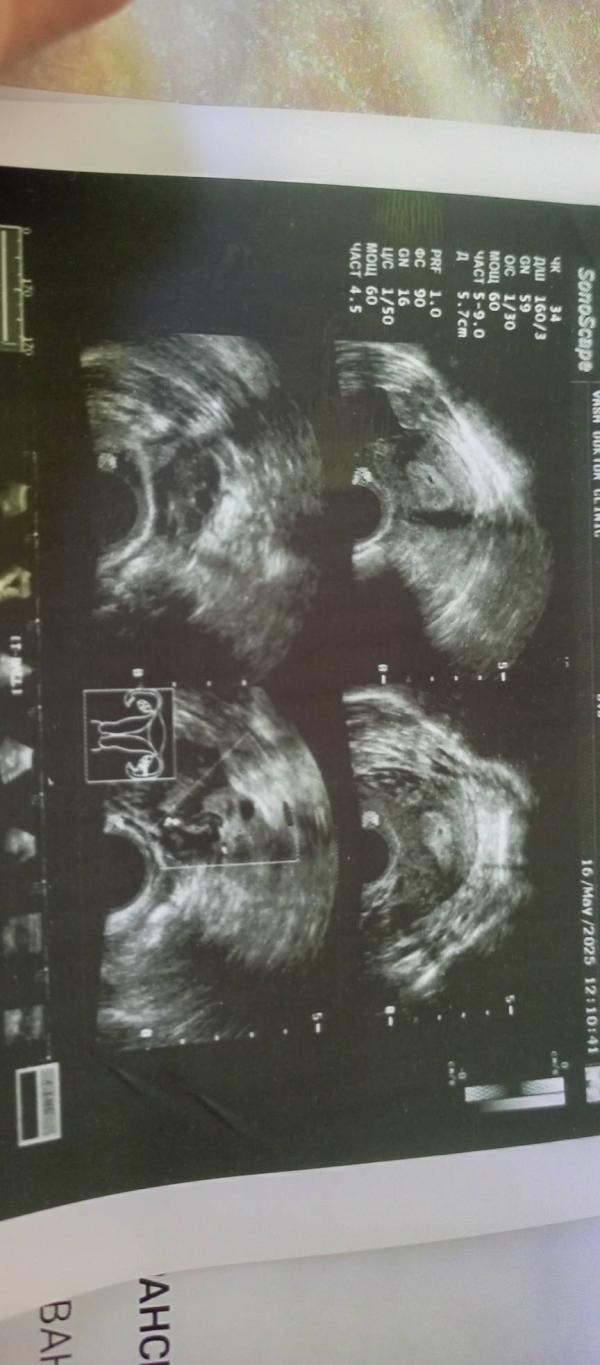

post image 1

Всё таки овуляции была на 20 дц🥰 надемся на чудо